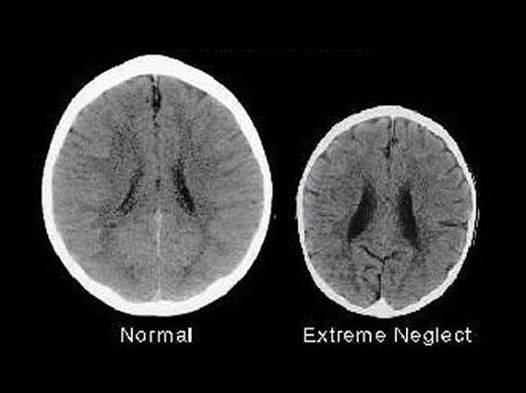

Brain imaging technologies allow researchers to look inside the brain to see the effects of injuries, diseases, drugs, chemicals — and parental neglect. These two scans both belong to three-year-olds, so why is one so much bigger? Because one was loved by their parents and the other was neglected.

The chilling images reveal that the left brain, which belongs to a typical three-year-old, is significantly larger and contains fewer spots and dark “fuzzy” areas than the right brain, which belongs to that of a three-year-old who has suffered extreme neglect.

Neurologists say that these images provide more evidence that how children are treated in their early years is essential for their emotional development and for determining their brain size. Experts say that the sizeable difference in the two brains is primarily caused by the difference in how each child was treated by their mothers.

While at first glance, the images might indicate that the child with the right brain might have suffered a serious accident or illness, neurologists said that the truth is that the child with the shrunken brain was neglected and abused by their mother. The child with the larger and more fully developed brain was raised in a loving, supportive home and was looked after by their mother.

According to researchers, the image of the brain scan on the right shows that the child lacks some of the most fundamental areas in the image of the brain scan on the left. They say that the child on the left with the larger brain will be more intelligent and more likely to develop the social ability to empathize with others than the child on the right.

On the other hand, the child with the smaller brain on the right will be more likely to become addicted to drugs, be involved in violent crimes, be unemployed, and be dependent on government benefits in the future. Furthermore, the child with the shrunken brain is significantly more likely to develop mental and other serious health-related problems.

Professor Allan Schore from the University of California, Los Angeles (UCLA) said babies rely on a strong bond with their mothers for healthy brain development in their first two years. “The development of cerebral circuits depends on it,” he said, adding that because 80 percent of brain cells grow in the first two years of life, problems in that development can affect people for the rest of their lives.